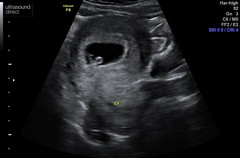

Really good news at my scan! Measuring 8 weeks 2 days. Could see the heart beating like mad and little gummy bear was wriggling around! Been discharged from EPU back to normal midwife care and have my booking in appointment next week. Makes this awful sickness completely worth it ! I’m also addicted to orange squash, hadn’t heard that old wives tale before! But as long as it’s healthy :) hope everyone’s feeling ok and that other scans go well xxx